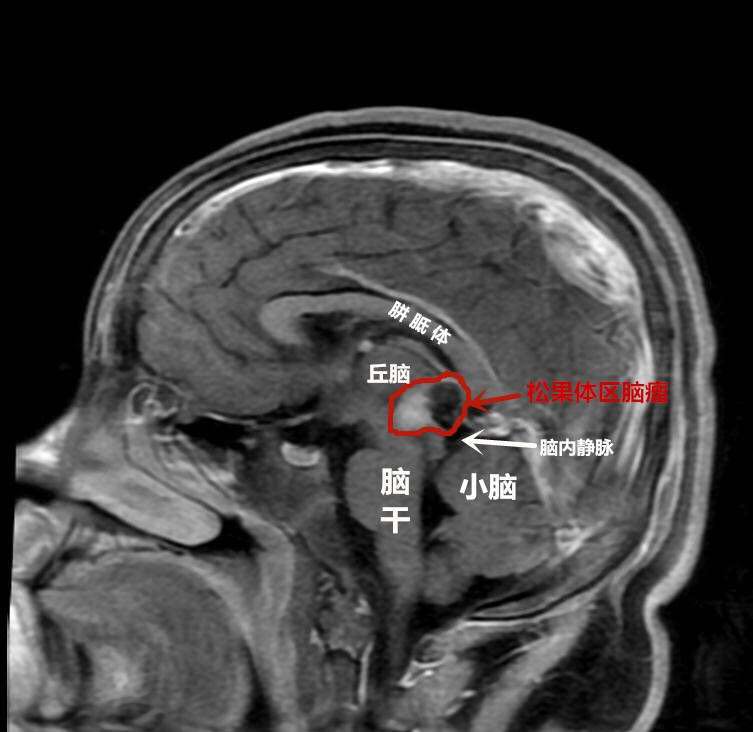

术前

为求进一步治疗,当天夜里他们便辗转到武汉脑科医院·长江航运总医院小儿神经外科。此时,军军随时都有生命危险,该科专家邵强主任连夜组织急诊手术。好在通过抢救及时保住了孩子的生命,一周后随着颅内压降低,邵强团队为军军进行了开颅手术,进行了分块全切脑瘤。邵强称,虽然患儿的肿瘤体积不大,但稍有不慎就会损伤正常脑组织和血管,引发昏迷,甚至大出血,可谓危险重重。